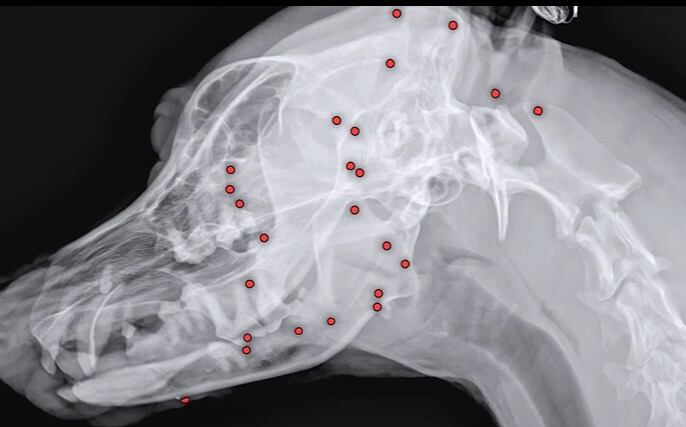

영상에 따르면 최근 구조된 유기견 백구의 몸에서 70개가 넘는 산탄총 파편이 박혀 있었다. 구조 당시 백구의 겉모습으로는 총알 자국을 확인하기 어려웠다. 하지만 해외 입양을 앞두고 건강검진을 위해 X레이 촬영을 했다가 산탄총 파편을 발견된 것이다.

병원 측은 곧바로 엑스레이, CT(컴퓨터 단층촬영) 등 정밀 검사에 들어갔다.

안승엽 VIP동물의료센터 원장은 “총알이 머리 쪽부터 어깨, 가슴통, 엉덩이, 다리까지 너무 많이 있었다”며 “살아있는 게 기적”이라고 전했다.

백구의 산탄총 파편 제거 수술은 3시간 넘게 진행됐다. 맨눈으로 탄알을 다 확인할 수 없어서 투시기를 이용해 수술을 진행했다.

안 원장은 “탄알을 한 번에 다 제거하기는 현실적으로 어려워 백구의 얼굴을 위주로 최대한 많이 제거하는 방향을 선택했다”며 총 26개의 파편을 제거했다고 설명했다.